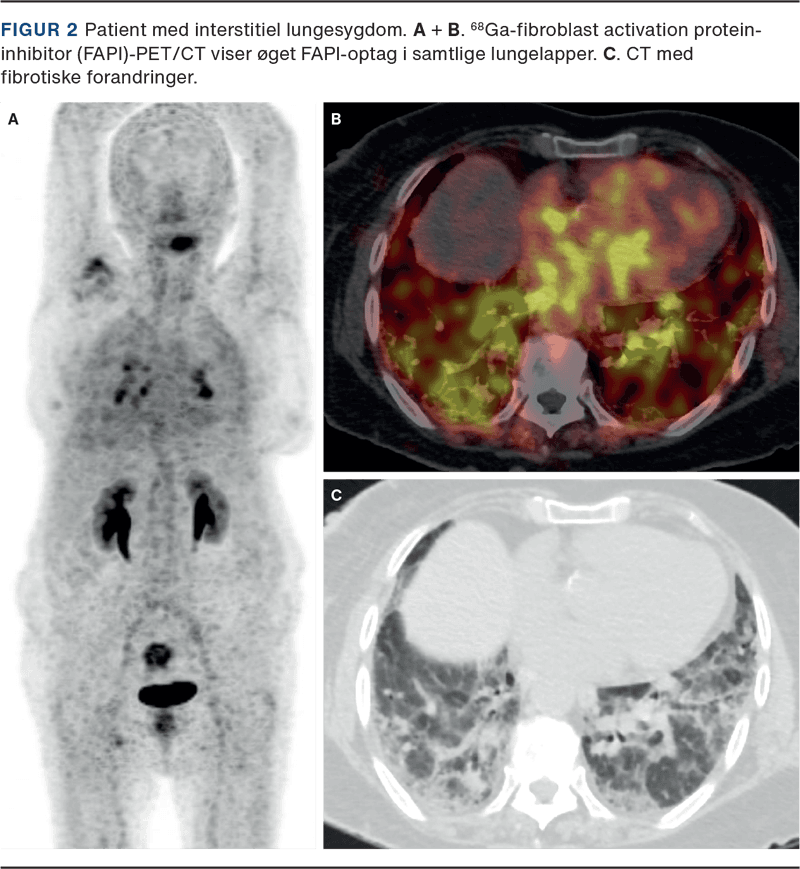

FAPI-PET er en ny type PET, hvor man bruger FAP-specifikke inhibitorer koblet til et radioaktivt sporstof (Figur 1). FAPI binder til FAP på de aktiverede fibroblaster, og med PET kan det visualiseres, hvor i kroppen der findes aktive fibroblaster, og ved måling af signalets intensitet kan det estimere graden af aktiv fibrose (Figur 2). Aktuelt er 68Ga-FAPI-46 den mest udbredte FAP-tracer, men der er udviklet flere andre, inklusive nogle, der bruger det radioaktive sporstof 18F, som er udbredt og tilgængeligt, da det f.eks. bruges til bl.a. fluorodeoxyglukose (FDG)-PET [4].

ILS er en gruppe af alvorlige sygdomme, hvor fibrotiske processer med eller uden ledsagende inflammation destruerer lungevævet. En stor udfordring i håndteringen af ILS er manglen på gode værktøjer til at monitorere sygdomsaktivitet og behandlingseffekt. P.t. bruges primært højopløsnings-CT (HRCT) og lungefunktionsundersøgelse (LFU), men disse modaliteter afspejler overvejende den irreversible skade, der allerede er sket på lungevævet. Det er ved ILS vanskeligt at vurdere sygdomsaktivitet, forudsige, hvilke patienter der vil have gavn af antifibrotisk behandling, samt identificere patienter, som ikke responderer på behandling rettidigt. FAPI-PET synes at have stort potentiale til netop dette. En række studier har vist, at patienter med ILS har højere FAPI-optag i lungerne sammenholdt med raske kontrolpersoner [8-11]. FAPI-optag korresponderer med fibrotiske foci på HRCT (Figur 1) og aktiv fibrosering ved histopatologiske undersøgelser, f.eks. i lunger udtaget ved transplantation [8, 11]. Flere studier har derudover påvist sammenhæng mellem øget FAPI-optag og nedsat forceret vitalkapacitet (FVC) og diffusionskapacitet. Lovende er det også, at flere studier viser sammenhæng mellem FAPI-signal ved baseline og efterfølgende sygdomsprogression [8, 12, 13].